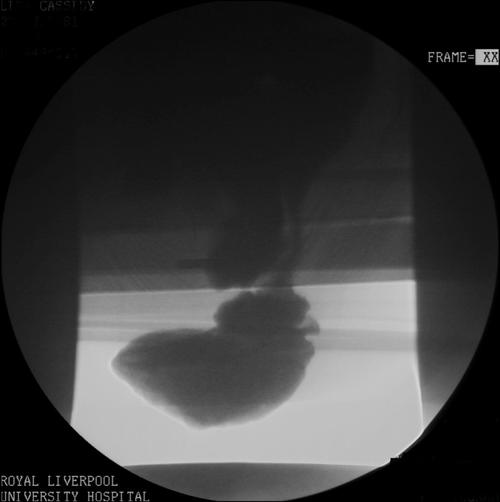

To achieve opacification of small bowel loops in fluoroscopic proctography, approximately 300ml of oral barium suspension is given 45 minutes prior to the beginning of the procedure. This is useful for the diagnosis of possible enterocoele (loops of small bowel in the pelvis). An initial digital rectal examination is performed with the patient in left lateral decubitus position in order to assess the tone of the sphincter complex and to confirm the safety of inserting a rectal tube. Approximately 200-300ml of thick barium paste is injected into the rectum via the tube. The entire examination is recorded through videofluoroscopy. Several video recorded images are obtained in left lateral and in supine positions with the patient responding to requests of ‘squeeze up’, ‘bear down’ and ‘cough’. This is to evaluate the response to increased intra-abdominal pressure. Subsequently, the patient is asked to sit on a specially designed chair and is instructed to empty the rectum completely. This part of the procedure is also video recorded and additionally spot images taken. The whole examination lasts approximately 10-15 minutes. Evaluation of the posterior compartment (rectum) with assessment pelvic floor descent is assisted by using an imaginary line drawn in the lateral views from the pubic bone anteriorly to a fixed segment of coccyx posteriorly (Figure 1).

Figure 1b: Pelvic floor descent with an enterocoele.

Figure 1c: Intussusception on fluoro proctogram.